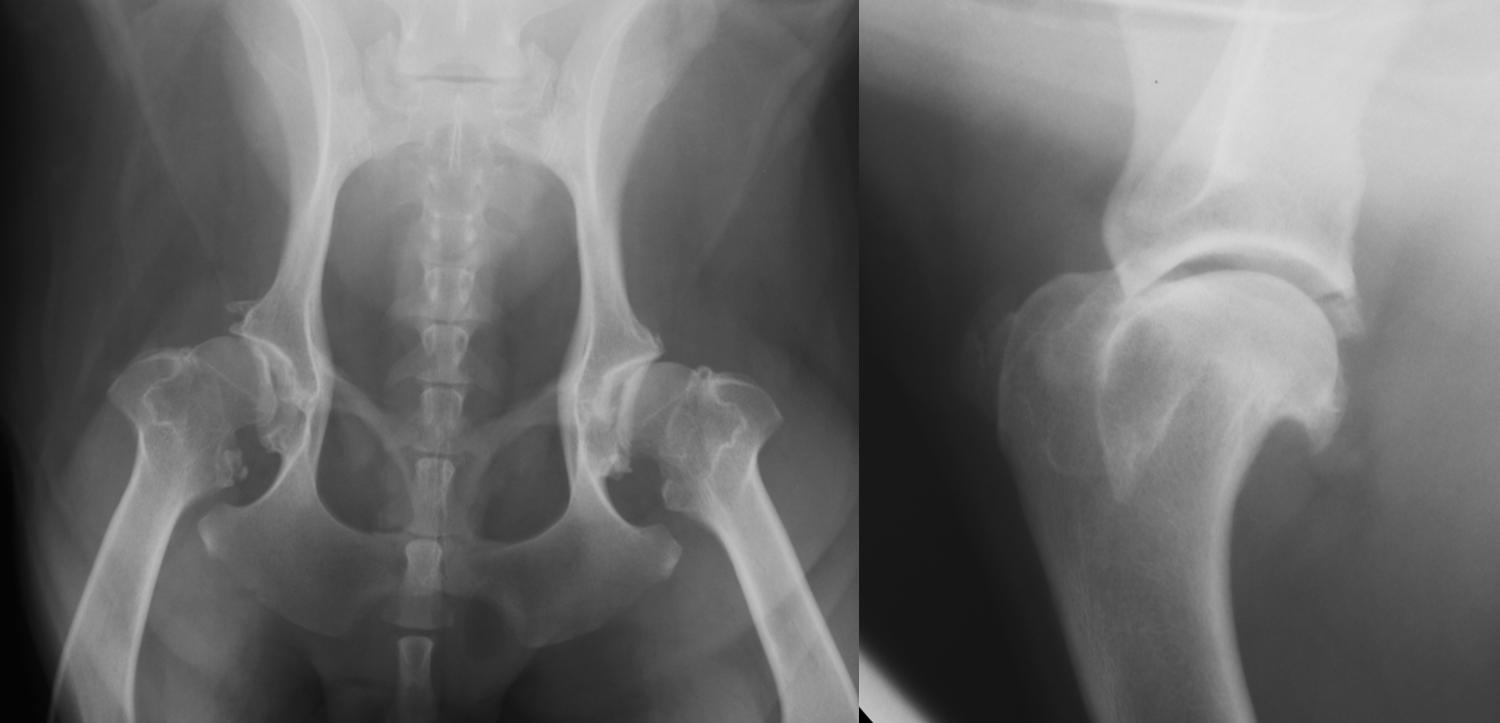

hip dysplasia signalment

large breed dogs

bilateral - inherited

flattened acetabulum, bad femoral head coverage, osteophytes along rim, morgans line

hip dysplasia

morgans line - early sign of DJD

what are the 3 views PennHip wants for hip dysplasia

extended leg VD

compression VD

distraction VD

calve legg perthes signalment

immature toy/small dogs

unilateral

increased joint space, irregular femoral head

calve legg perthes